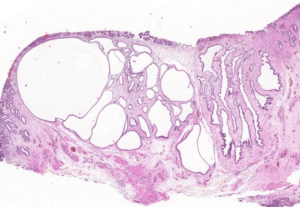

Chronic polypoid cystitis is characterized by the presence of polypoid masses, particularly common in dogs but may occur in any species. These masses likely develop as an inflammatory and hyperplastic response to chronic irritation, often stemming from persistent bacterial urinary tract infections (UTIs) and/or uroliths.

The polyps found in the bladder mucosa consist of a core of proliferative connective tissue covered by surface epithelium. This surface epithelium can form nests of hyperplastic urothelial cells in the lamina propria, known as Brunn’s nests, or undergo metaplasia to a mucus-secreting, glandular epithelial type, leading to a condition called CYSTITIS GLANDULARIS. These resulting polypoid masses may have a broad-based or pedunculated structure, occurring most frequently in the cranioventral bladder wall. Chronic haematuria, often unresponsive to antimicrobial therapy, is a common observation in cases of chronic polypoid cystitis. This bleeding is often associated with the breakdown of polyps, potentially promoting urine retention and bacterial introduction, thus establishing a cyclic pattern of infection, proliferation, and inflammation.

Histologically, our case had in lamina propria, occasionally extending from mucosa, multiple hyperplastic tortuous glands that were often cystic dilated. They were lined by one to multiple layers of uniform cuboidal or columnar epithelial cells, occasionally surrounded by a few layers of urothelial cells. They had no evident atypia. The lamina propria where they were immersed contained a few plasma cells, lymphocytes, neutrophils and rare histiocytes.